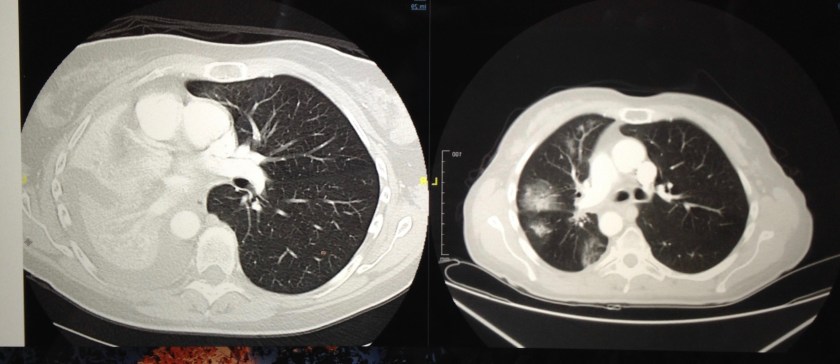

Below: February 2016 and May 2016 after two months on my first targeted therapy, crizotinib.